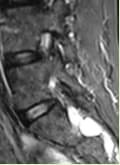

Investigations included MRI of the Lumbosacral spine which showed a large Tavlov Cyst at S1 on the right and S2 on the left. There was no bony erosion.

MRI of the cervical gland thoracic spine showed no neural compression. MRI of the right thigh and hip showed mild hip effusion but was otherwise normal.